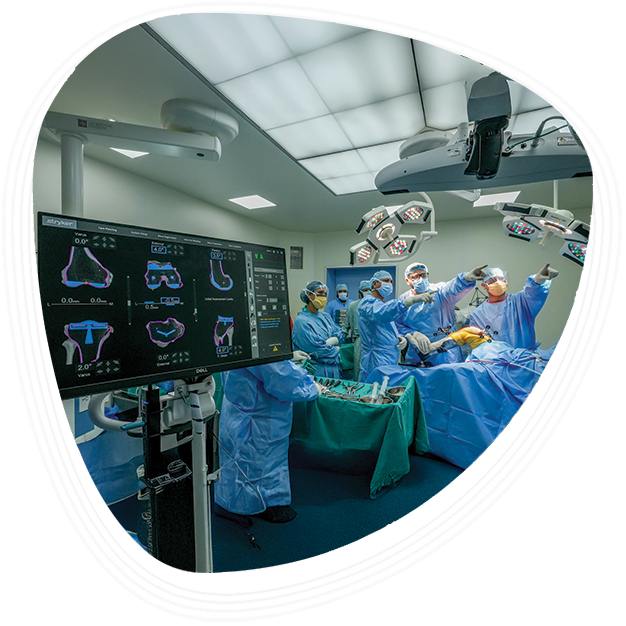

Robotic-Assisted Joint Replacement

As a leader in joint replacement surgeries, we offer robotic-assisted options. This advanced technology enables high precision, shorter recovery times, and better postoperative outcomes.